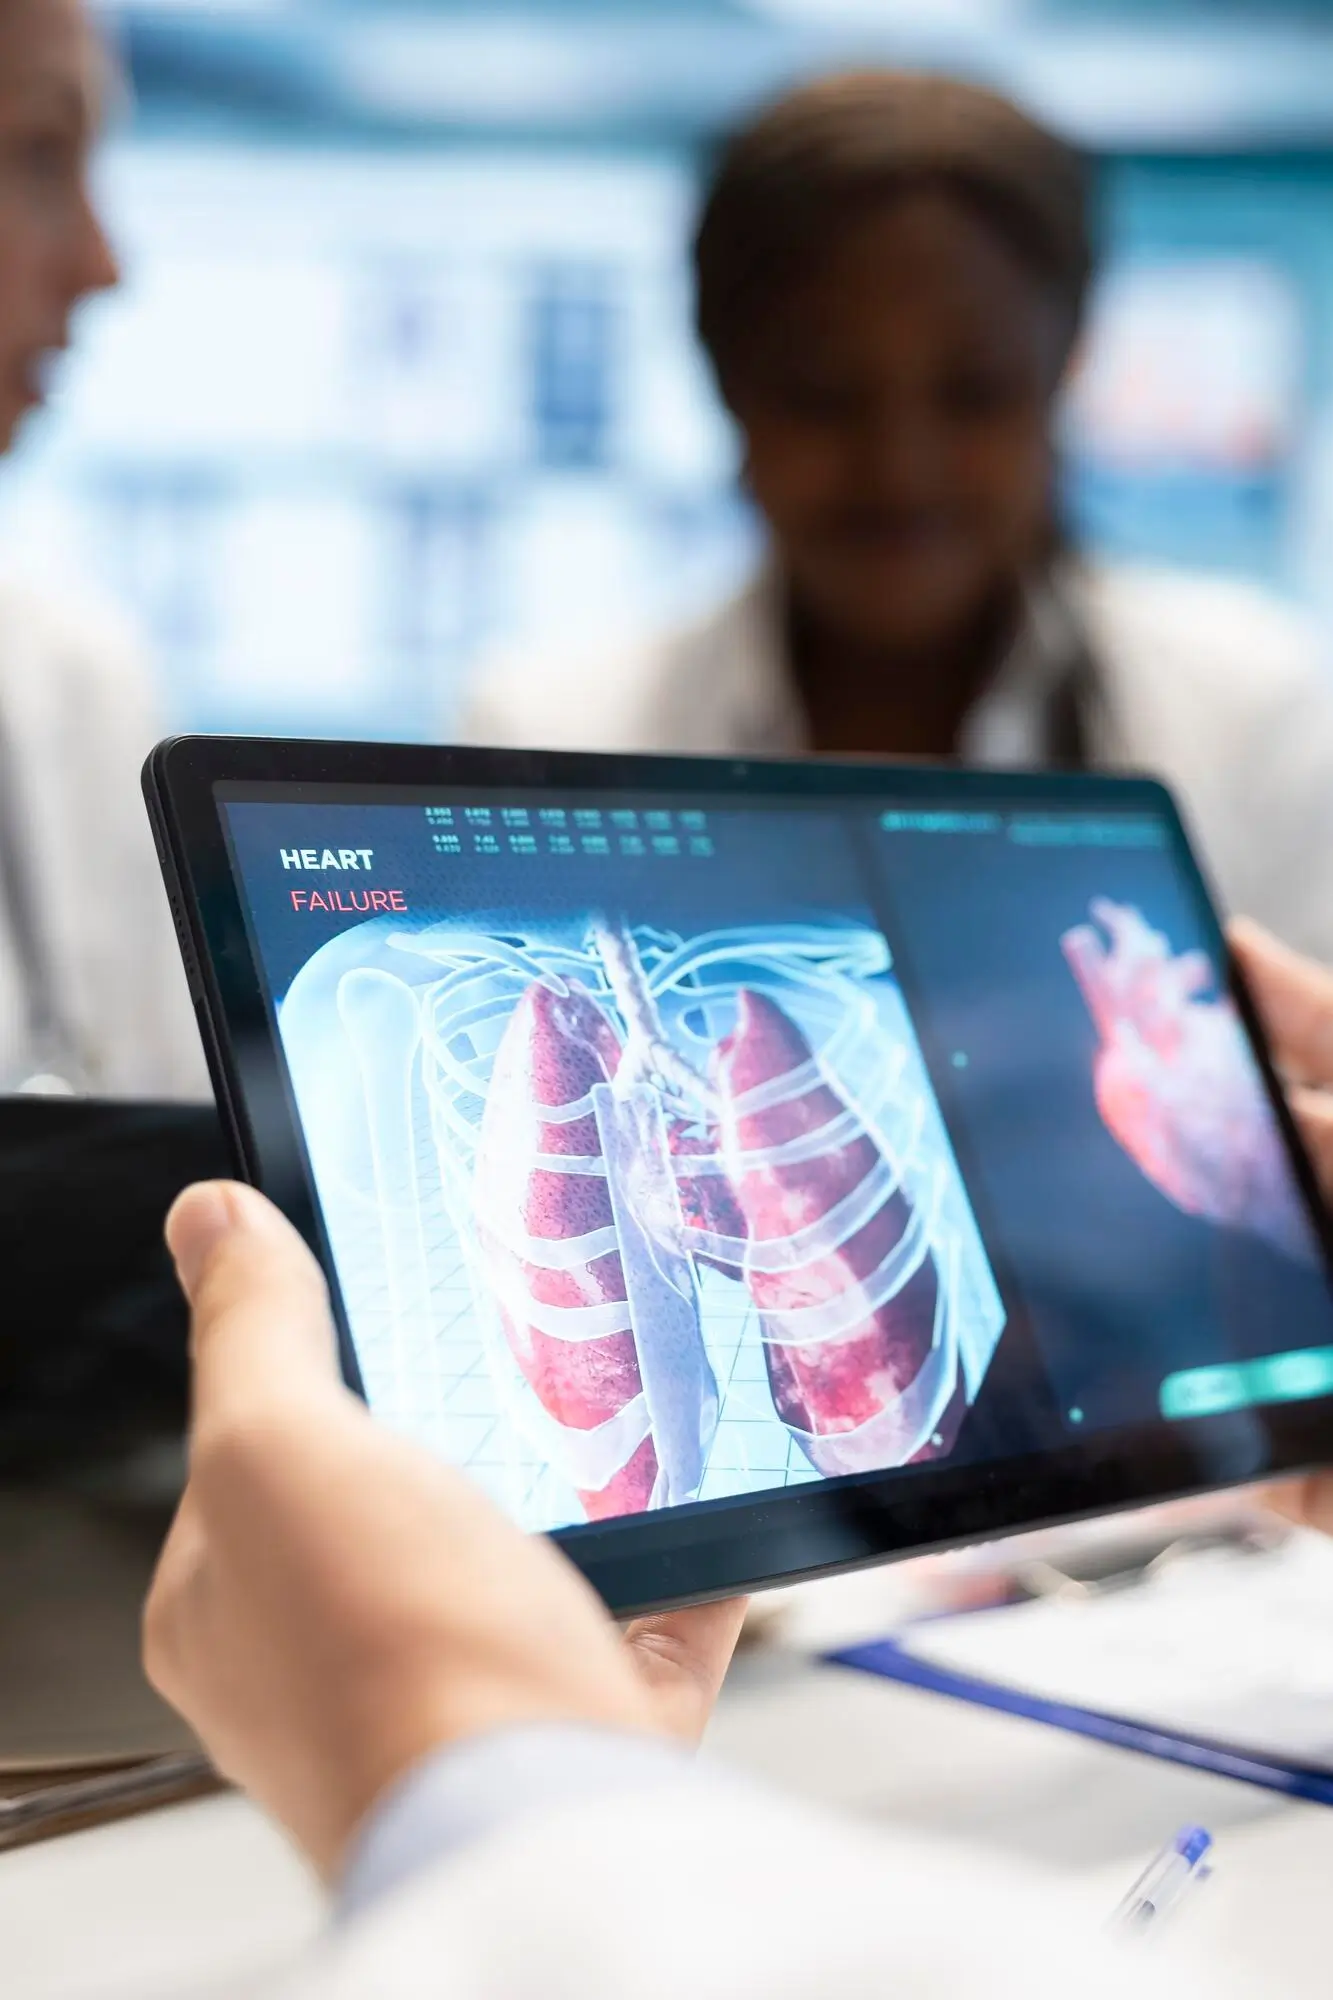

We Are A Clinic, Provide Excellence In Personalized Care

We are a private, independent practice constantly striving to provide excellence in personalized, compassionate care that is consistent, quality-driven and choice-conscious for all of our patients.

We welcome advances in learning and technology in an effort to achieve efficient and quality-driven patient care.

Together our team of doctors bring a broad spectrum of experience and professional expertise and continually undertake professional development education to remain up to date with the latest in medical treatment options.